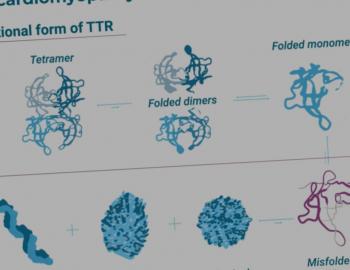

Voor deze aandoening is de behandeling gericht op het transthyretine-eiwit (TTR) dat zich verkeerd vouwt en opstapelt. Dat gebeurt met een transthyretine stabilisator.23

Deze stabilisator bindt zich selectief en met hoge affiniteit aan TTR (een tetrameer). Daardoor dissocieert het minder snel in monomeren. En dat draagt bij aan de stabiliteit van het eiwit. Die dissociatie is de snelheidsbepalende stap van het proces dat leidt tot de vorming van amyloïd. Dus daar ingrijpen vormt de rationale voor het gebruik van stabilisators bij patiënten met ATTR amyloïdose.23